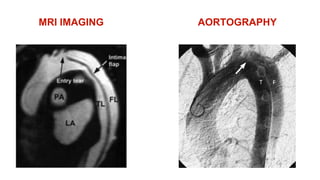

-MRI IMAGING:

- 99% SENSITIVITY

- BEST IMAGES AND DETAILS VISUALISED

- BUT:

- NOT ALWAYS AVAILABLE

- TIME CONSUMING METHOD

- CONTRAINDICATED IN HAEMODYNAMICALLY

UNSTABLE PATIENTS WITH IMPENDING RUPTURE,

CARDIAC TAMPONADE

-AORTOGRAPHY:

- 80% SENSITIVITY

- RARELY USED

- HISTORICALLY THE GOLD STANDARD

- MAY PRECIPITATE AORTIC RUPTURE

WHAT ARE THE DIFFERENT

CT WITH CONTRAST ENHANCEMENT